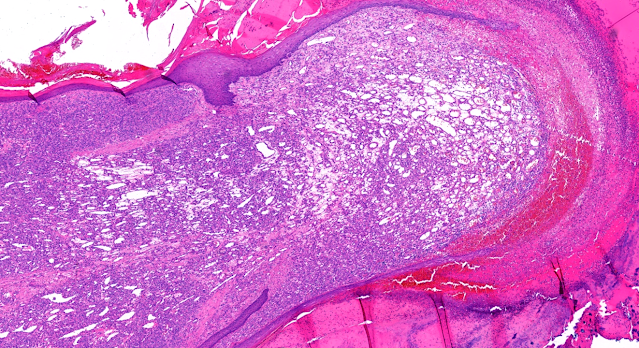

Dermatopathology Case 253 Get link Facebook X Pinterest Email Other Apps July 30, 2022 A 38 year old woman. Slide for diagnosis. Answer Get link Facebook X Pinterest Email Other Apps Comments